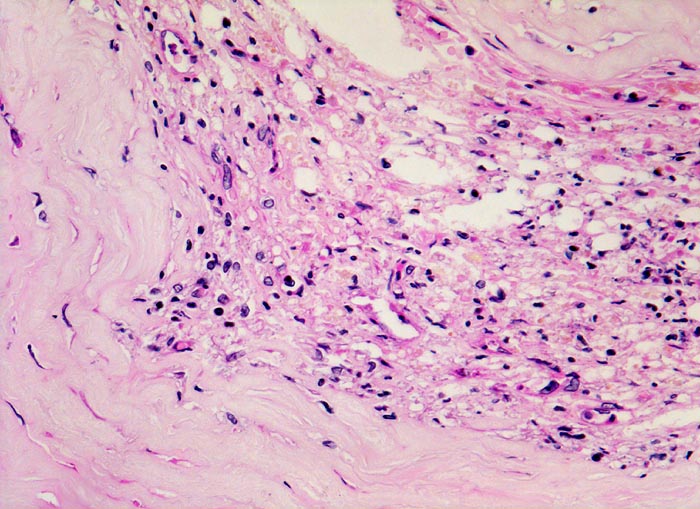

Koronarsklerose: Atherom

vaskulär / Durchblutungsstörung

Arteria coronaris

Kardiovaskuläres System

Ausschnitt aus der sklerosierten Intima mit Atherom: Herd von Granulationsgewebe mit Kapillaren und lockerem Infiltrat von Lymphozyten, Histiozyten und lipidbeladenen Schaumzellen.

Subakuter transmuraler Myokardinfarkt. In der Anamnese Nikotinabusus und schlecht eingestellte arterielle Hypertonie.

Histologie

320